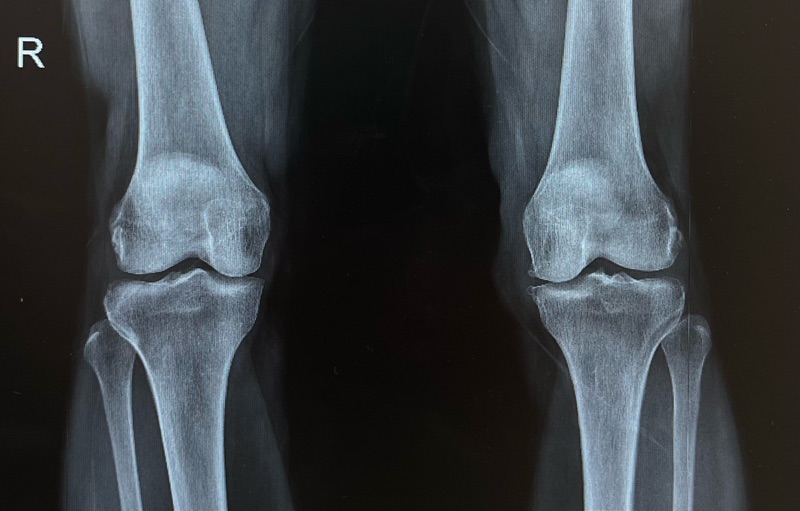

หลังตรวจพบว่าเข่าเสื่อมระดับปานกลาง หมออธิบายว่า อาหารเสริมไม่สามารถแก้ผิวข้อที่สึกแล้วได้ แต่เมื่อเริ่ม

เพราะ “ข้อเข่าเสื่อม” เกิดจากการสึกของกระดูกอ่อนผิวข้อ ซึ่งเป็นเนื้อเยื่อที่ ร่างกายไม่สามารถงอกใหม่แบบเดิมได้